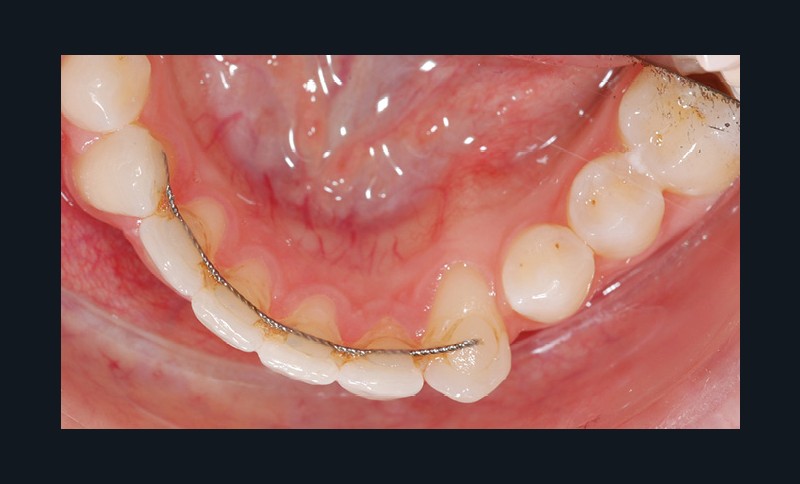

Par exemple, le retraitement d’un patient atteint d’un « Syndrome du fil » [2, 3], au vu de l’état des connaissances imparfaites de l’étiologie de cette situation, méritera une réflexion pour trouver un système de confiance. Une fibre collée est l’une des solutions sécurisantes (fig. 1). Mais, si la langue n’est pas stabilisée au repos comme en fonction, un dispositif amovible type Spring Retainer sera préférable.